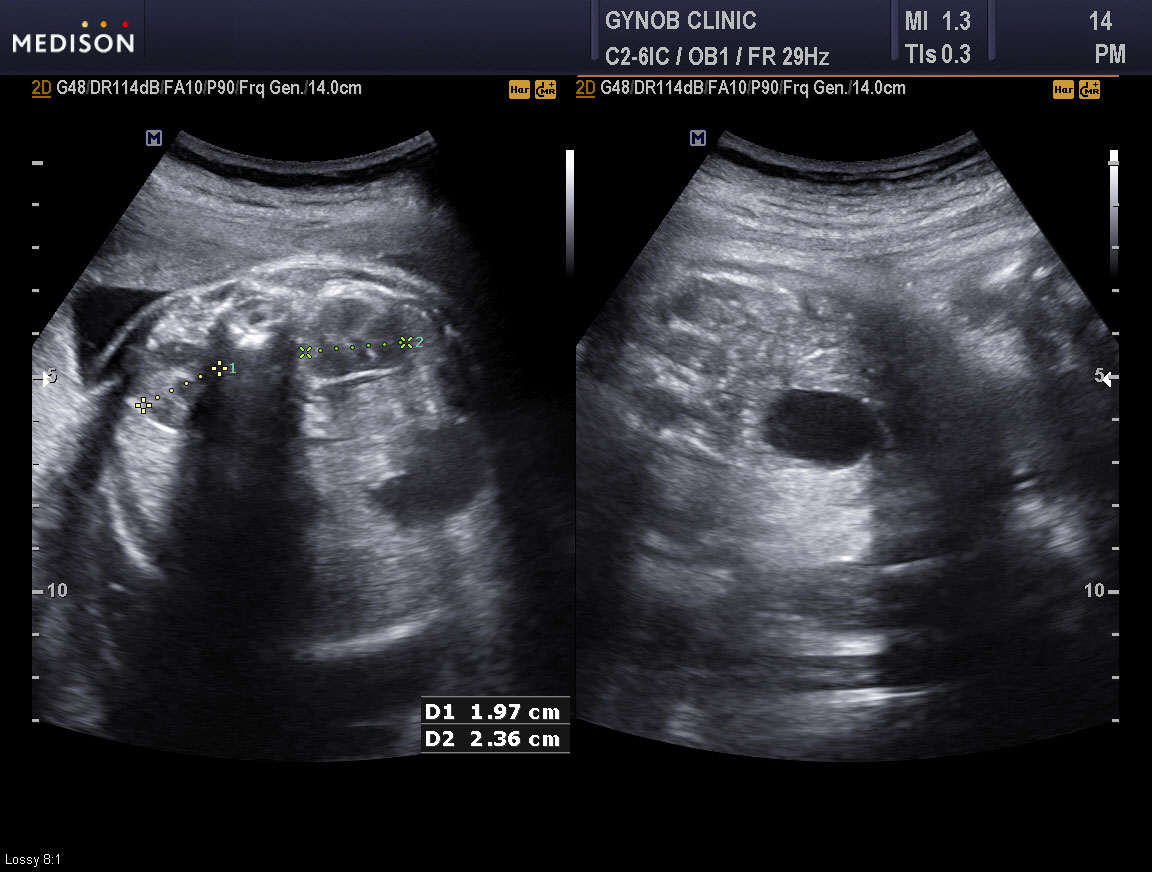

아래는 성균관 의대 (삼성 서울 병원 산부인과) 김문경 교수등이 2009년 대한산부인과 초음파 학회지에 발표한 관련 논문의 내용을 발췌한 것이니 참고하시기 바라며 사진은 저희 병원에서 찍은 초음파 사진으로 좌측은 정상 콩팥의 초음파 소견이고 우측의 까만 동그라미가 방광입니다.